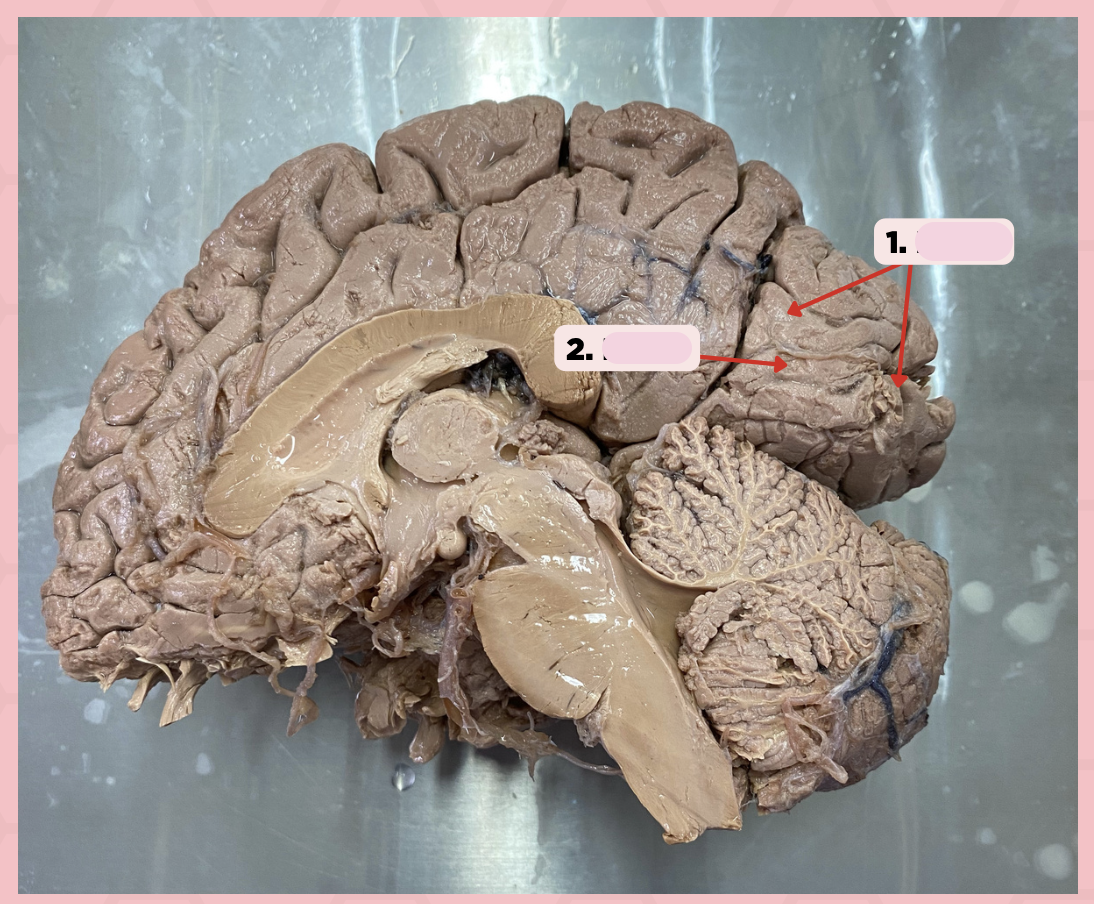

Identify the structure labeled as 1.

a. Pre-central gyrus

b. Post-central gyrus

c. Central sulcus

d. Pareto-occipital fissure

Pre-Central Gyrus

Post-Central Gyrus

Identify the structure labeled as 2.